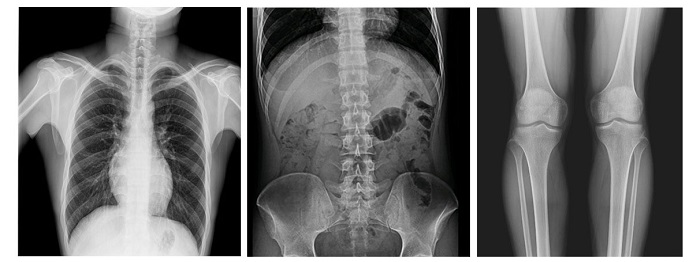

配備新一代動態(tài)平板探測器,17×17英寸大幅面成像,能對患者的胸部腹部等部位實現(xiàn)大范圍全覆蓋,透視檢查無需對患者重新定位便可觀察到足夠大的人體器官組織,避免漏診誤診;最高30幀/s采集幀速,影像更加流暢,便于使醫(yī)生觀察細微病變,從而提高診斷準確率。